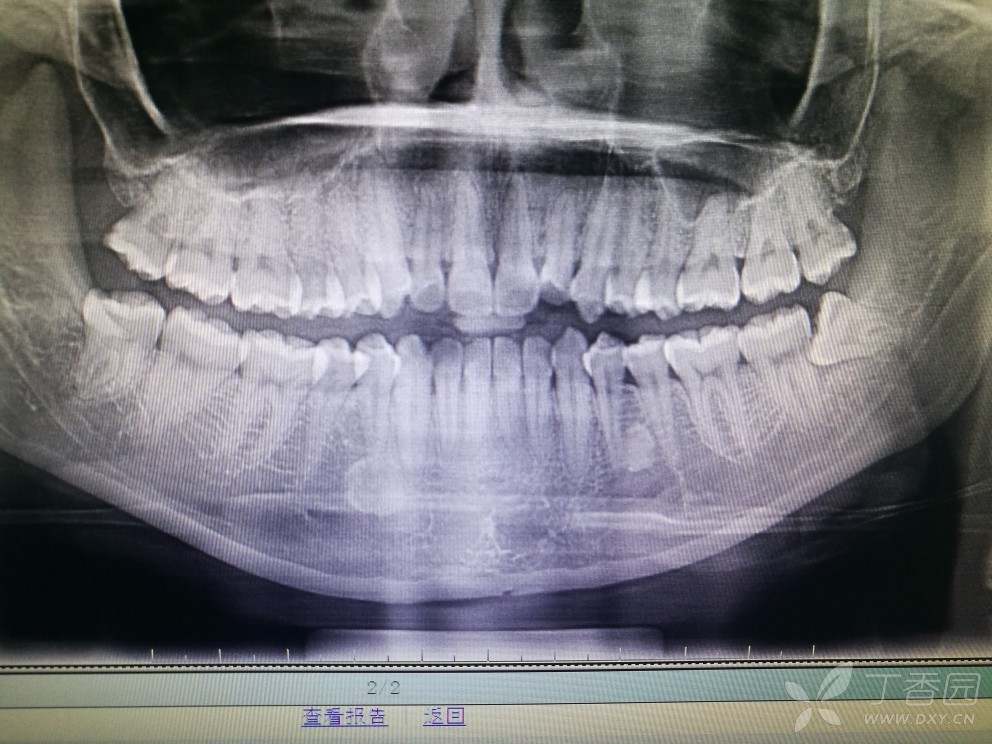

智齿片子,正常智齿片子

本人昨天去医院拍的片子,如果把左下智齿拔了,左上的智齿用拔吗,左下

我的下面两颗智齿长这样需要拔除吗?从片子上看完全是

【关于智齿】昨天去医院拍了片,长了四颗智齿,下排的两个智齿虽长歪了

智齿一定要拔么?(有全片)?

有谁能告诉我这片子看得出是否有蛀牙吗?智齿已经拔了

正常智齿片子

智齿的x光片

水平阻生智齿

智齿片子图片

智齿拍片

智齿x光片